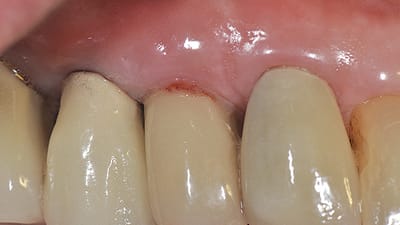

Case Report Case Studies Clinical Implications of Peri-Implant Disease Paul S. Rosen, DMD, MS, Stuart J. Froum, DDS Guidelines to prevent and treat biologic complications September 01, 2014 11 min read

Practical Application Peri-Implant Disease: Diagnosis, Treatment, and Prevention Protocol Lauren E. Anderson, DDS, MS Periodontitis correlations aid in disease management September 01, 2014 10 min read

Maintenance Peri-Implant Disease: Current Considerations and Parameters for Care Christopher R. Richardson, DMD, MS September 01, 2014